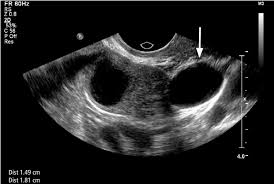

Fluid accumulation in the cul-de-sac, also known as Douglas’s pouch, can occur due to various reasons. One common cause is ovarian cysts. These fluid-filled sacs on the ovaries can rupture or leak, leading to free fluid in the cul-de-sac.

Let’s explore the connection between ovarian cysts and fluid accumulation in the cul-de-sac in more detail. Imagine the ovaries as two small organs nestled within the pelvic cavity. They produce eggs and hormones essential for the female reproductive system. Sometimes, fluid-filled sacs, known as cysts, can develop on the ovaries. These cysts can vary in size and can either be benign (non-cancerous) or malignant (cancerous).

Now, let’s focus on the scenario of a ruptured or leaking ovarian cyst. When a cyst ruptures, the fluid inside spills out, creating a pool of free fluid in the pelvic cavity. This fluid finds its way to the cul-de-sac, the lowest point in the pelvic cavity, where it can accumulate. The amount of fluid accumulation can vary depending on the size of the ruptured cyst.

In most cases, the fluid in the cul-de-sac is benign and will be absorbed by the body naturally. However, if the fluid is significant or if the cyst is cancerous, it can cause symptoms like abdominal pain, bloating, or irregular bleeding. In these situations, medical intervention may be necessary to drain the fluid and address the underlying cause.

Remember, this information is for general knowledge and does not substitute professional medical advice. If you have any concerns about fluid accumulation in the cul-de-sac, it is essential to consult your doctor for proper diagnosis and treatment.